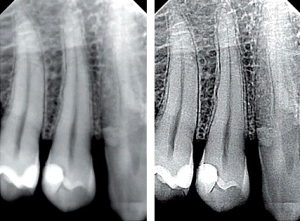

Digitalnim radiografisanjem zuba u stomatološkoj ordinaciji Numanović možemo preciznije dijagnostikovati probleme sa zubima. Ova oprema sa niskim zračenjem omogućava našim stomatolozima da pregledaju mjesta u ustima koja inače ne mogu da vide golim okom.

Digitalni rendgenski snimci su jedan od naprednih dijagnostičkih alata koje koristimo da bismo Vam pružili najbolju moguću njegu. Digitalna radiografija je promijenila način na koji snimamo zubne rendgenske snimke čineći proces bržim, udobnijim i praktičnijim nego ikada ranije. Digitalni rendgenski snimci koriste digitalni senzor za snimanje Vaših zuba, za razliku od tradicionalnih rendgenskih aparata koji koriste film. Digitalni rendgenski zraci koriste znatno manje zračenja od konvencionalnih filmskih rendgenskih zraka i ne zahtjevaju upotrebu hemikalija za razvijanje slika. Dr Numanović može odmah da vidi visokokvalitetne slike na monitoru.

Digitalna radiografija može pomoći u dijagnostici stomatoloških problema, kao što su:

- karijes između zuba

- abnormalnosti u razvoju

- nepravilan položaj korijena zuba

- ciste i apscesi

- prelomi u postojećim plombama

- tumori

- infekcija u nervima zuba

- gubitak kosti